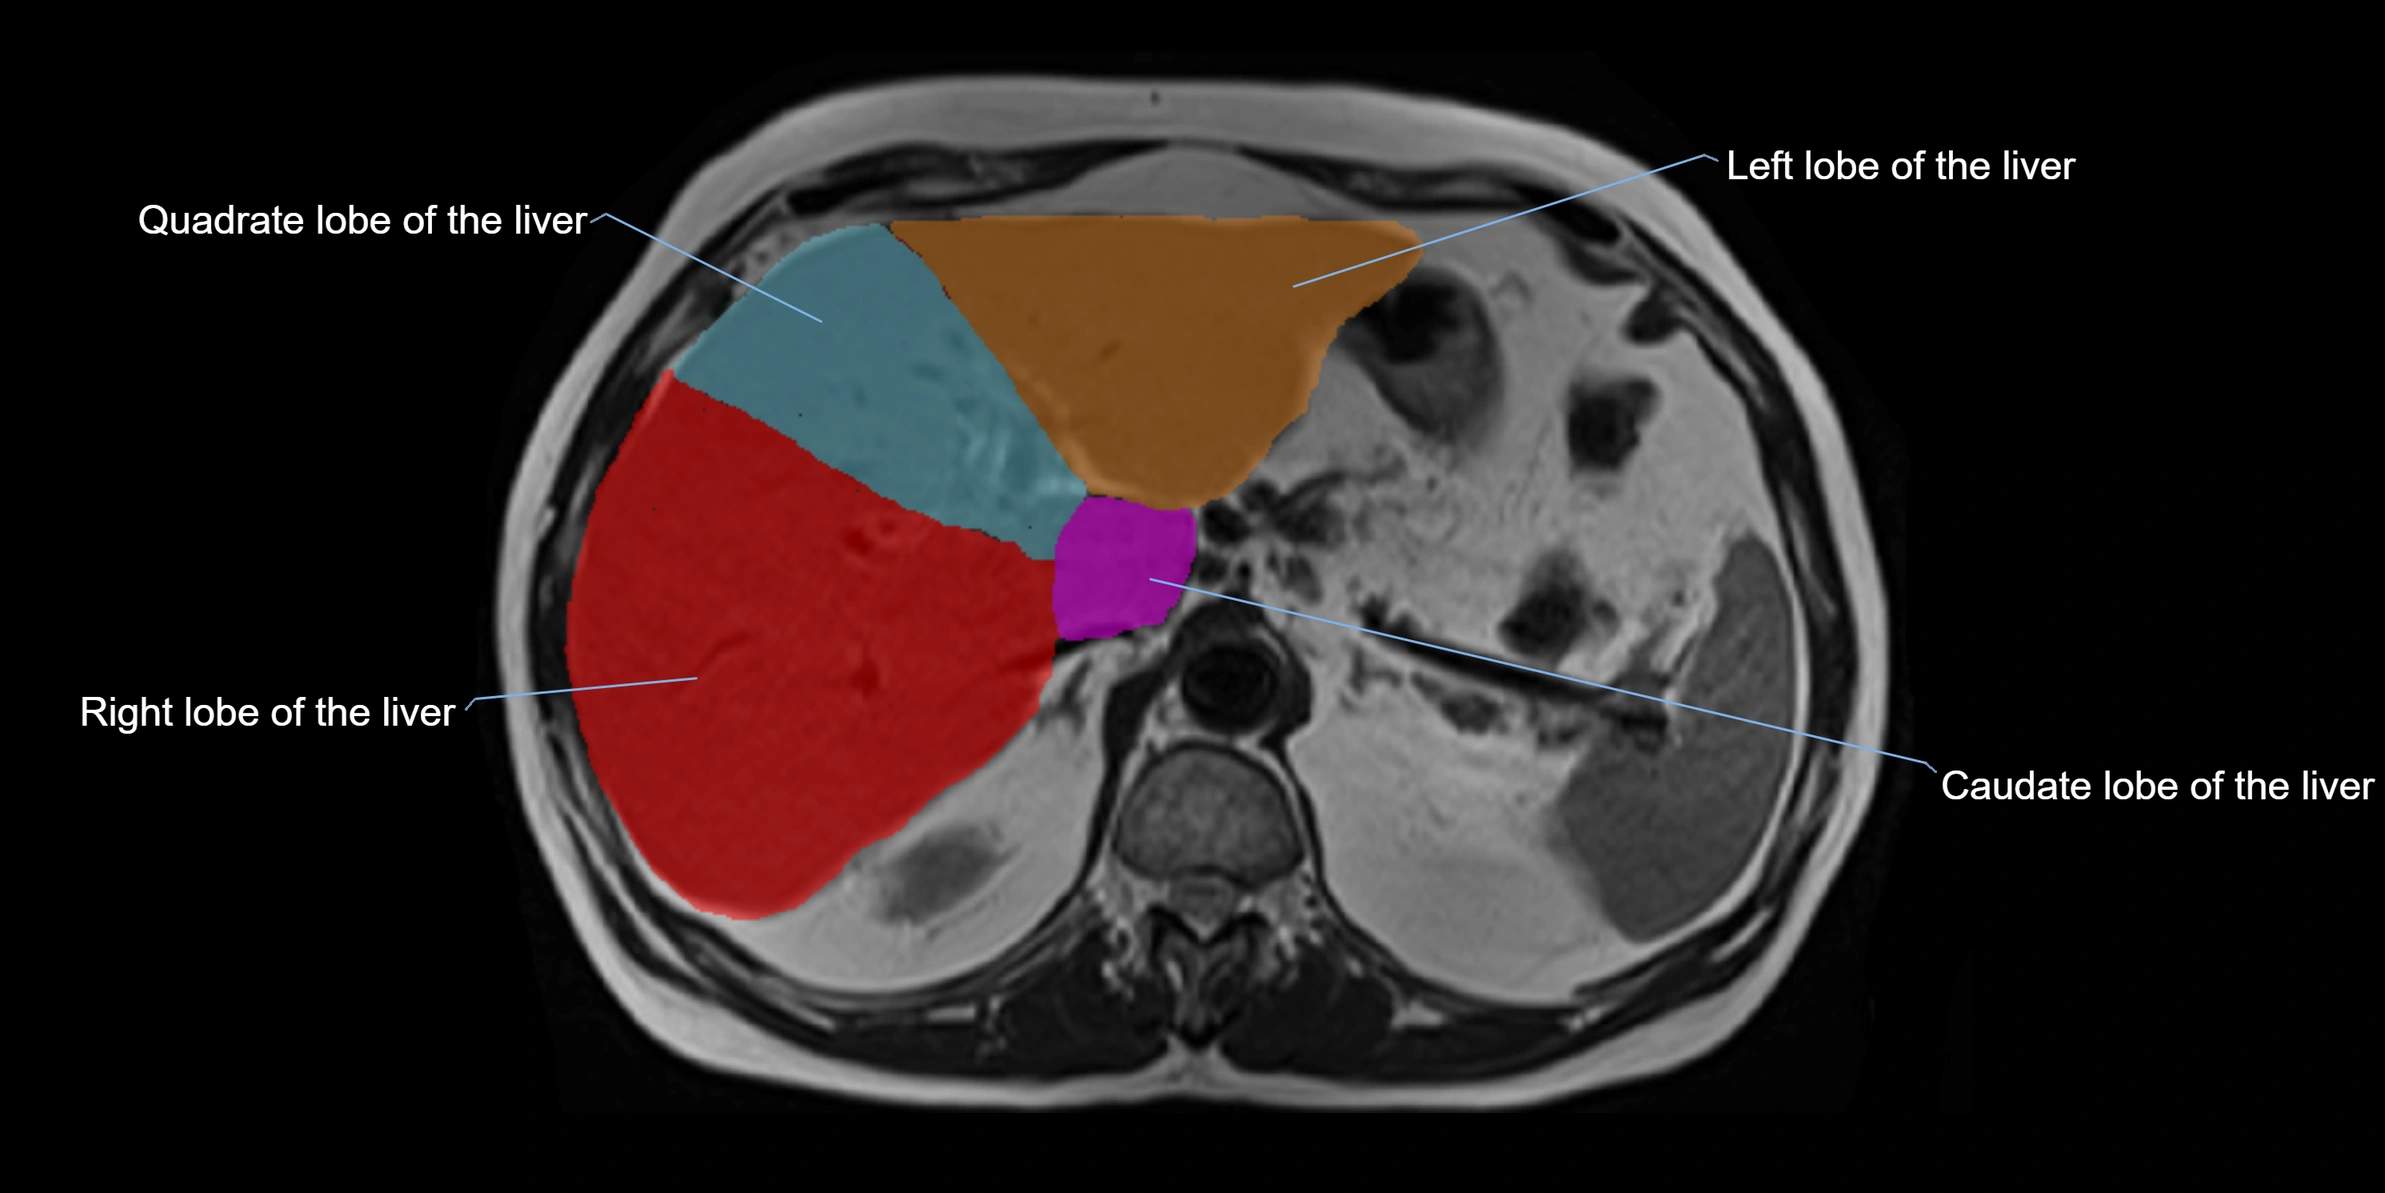

The caudate lobe of the liver is a distinct anatomical subdivision of the liver, designated as segment I in Couinaud’s classification. It lies on the posterior surface of the liver, between the fissure for the ligamentum venosum (left boundary) and the groove for the inferior vena cava (IVC) (right boundary). Superiorly, it is related to the posterior liver surface, and inferiorly it is separated from the left lobe by the porta hepatis.

The caudate lobe is unique because it receives dual portal venous and arterial inflow from both the right and left portal veins and hepatic arteries. It also has independent venous drainage directly into the IVC via multiple small hepatic veins, unlike other lobes that drain through the three main hepatic veins.

This anatomical autonomy makes the caudate lobe especially significant in liver surgery, transplantation, and hepatic venous outflow obstruction syndromes (e.g., Budd–Chiari syndrome). Enlargement of the caudate lobe is a characteristic imaging feature in chronic liver disease and cirrhosis.